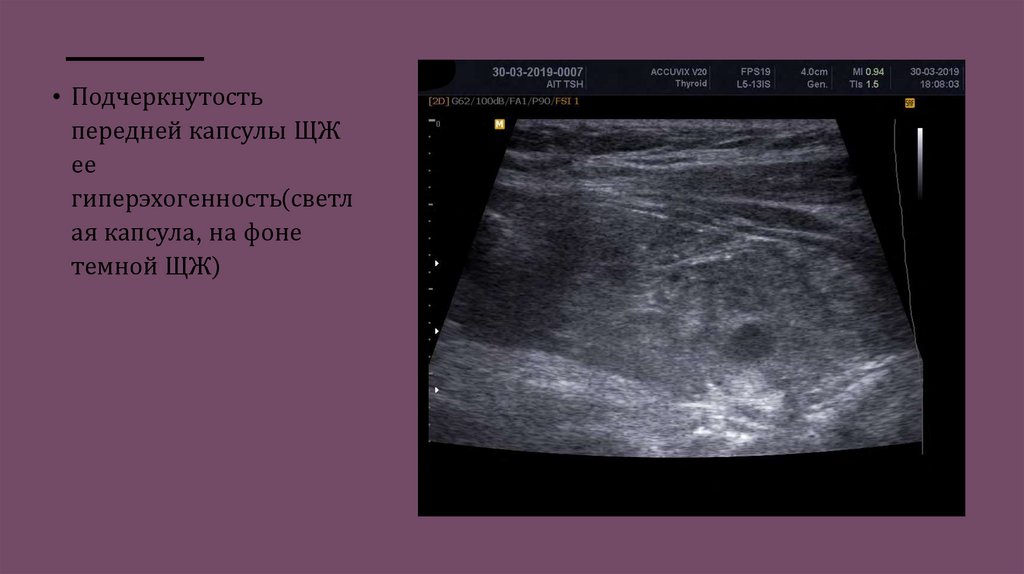

• Подчеркнутость

передней капсулы ЩЖ

ее

гиперэхогенность(светл

ая капсула, на фоне

темной ЩЖ)